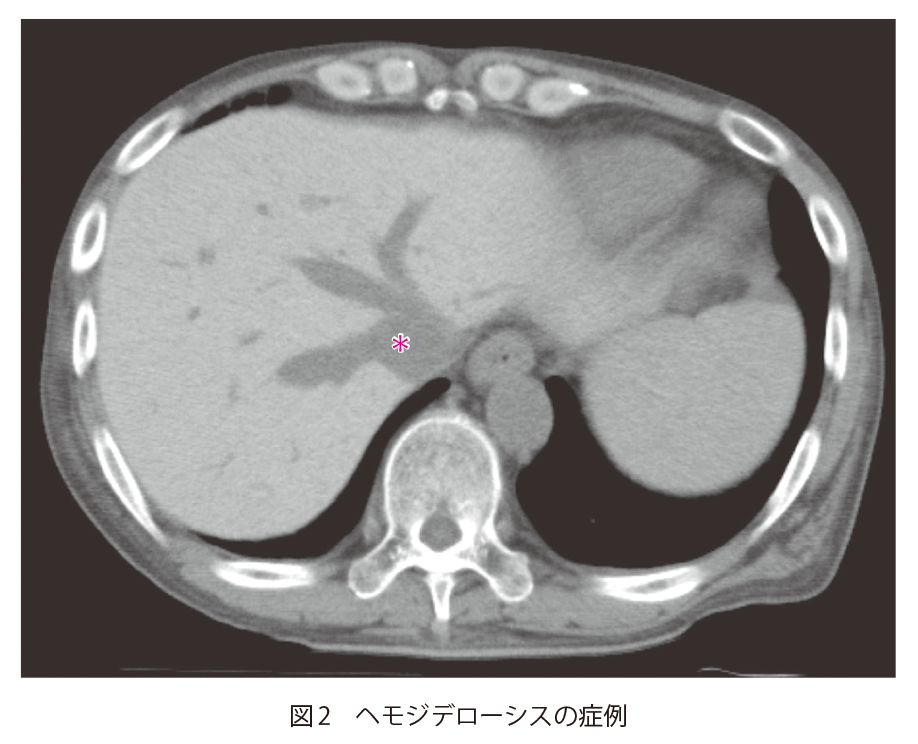

閉塞性肥大型心筋症で通院中の70歳代男性 70歳代男性.閉塞性肥大型心筋症で定期受診中.数年前に植込み型除細動器(implantable cardioverter defibrillator:ICD)を植込み済.数日前より便秘,腹部膨満感,腹痛があり来院.腸閉塞が疑われ,精査のために単純CTが撮影された. A1.肝実質がびまん性に高吸収になっているA2.アミオダロンや鉄剤の内服歴,頻回の輸血歴などがないかを確認するA3.アミオダロン肝 1.読影のポイント 単純CTで肝実質がびまん性に高吸収に描出されている.肝実質と門脈(図1▶︎),IVC(inferior vena cava:下大静脈,図1▶︎)とのコントラストが増強しており,脾臓(図1 S)と比較しても肝実質が高吸収になっていることがわかる.びまん性に濃度変化を生じていると,一目では変化に気がつかないことがある.比較画像がある場合はその画像との対比を,比較画像がない場合には周囲にある構造と濃度を比較することで,変化や異常に気がつきやすくなる.今回の場合では,肝実質と肝内血管の濃度差,肝実質と脾臓の濃度差に気がつけるかどうかが最大のポイントとなる. この症例では,ICDの植込み歴があり,アミオダロン肝と診断された.塩酸アミオダロンは抗不整脈薬の1つで,脂溶性のため,脂肪組織や肺,膵臓,肝臓,心臓,腎臓に蓄積されることが知られている.ヨードを含有しているため,肝臓に蓄積すると肝実質が高吸収を示す. 2.鑑別診断 単純CTで肝臓がびまん性に高吸収になる場合,原子番号が高い元素(鉄,金,銅,ヨードなどの金属)や高分子化合物が沈着していることが考えられる.鉄が蓄積するヘモクロマトーシス/ヘモジデローシス,銅が沈着するWilson病などが疾患としては有名である.これらは画像のみでの鑑別は難しく,臨床情報が非常に重要となる. 3.次の一手 診断には臨床情報が非常に重要である.特に内服薬や既往歴,頻回の輸血がないかどうかの確認が重要となってくる.既往に不整脈やペースメーカー/ICDの植込みがある場合にはアミオダロン内服によるアミオダロン肝の可能性を,鉄剤の内服や静注などがある場合にはヘモクロマトーシス/ヘモジデローシスを考慮する必要がある. 図2にヘモジデローシスの症例を示す.アミオダロン肝と同様に,肝臓がびまん性に高吸収になっており,肝内血管(図2*)とのコントラストが増強している.この症例では,頻回の輸血歴があり,血清フェリチン値も高値(>1,000μg/dL)を示しており,輸血後鉄過剰症と診断されている.ヘモクロマトーシス/ヘモジデローシスの診断にはMRIが有用で,鉄の沈着を反映して,T2強調像やT2*強調像で信号低下がみられる. 救急医Check Point アミオダロンは心室細動,心室頻拍や心不全(低心機能)または閉塞性肥大型心筋症に伴う心房細動などの再発性不整脈において他の抗不整脈薬が無効,または使用できない場合に使用される薬剤である.非常に有効な薬剤である反面,肺(間質性肺炎,肺線維症,肺胞炎),心臓(既存の不整脈の重度の悪化,Torsades de pointes,心不全,徐脈,完全房室ブロックなど),肝臓(劇症肝炎)などの致死的となりうる副作用が報告されている. アミオダロン肝は除外診断であるためで1),血液生化学検査によるトランスアミナーゼや肝炎ウイルスの検査などその他の原因による肝疾患の精査を消化器内科など専門医に依頼する必要がある.肺野病変を認める場合も呼吸器内科など専門医に紹介する.また,副作用の発現が疑われた場合,重篤化すると致死的となる可能性もあるため,処方医にアミオダロンの必要性について再検討を依頼し,肝臓,肺などの専門医と連携して薬剤量を調整してもらうように依頼する. 文献:1)Hussain N, et al:Amiodarone-induced cirrhosis of liver:what predicts mortality? ISRN Cardiol,2013:617943, 2013 文献・参考文献 「肝胆膵の画像診断-CT・MRIを中心に-」(山下康行/編著),学研メディカル秀潤社,2010 「腹部のCT第3版」(陣崎雅弘/編),メディカル・サイエンス・インターナショナル,2017 「肝胆膵のCT・MRI」(本田 浩,他/編),メディカル・サイエンス・インターナショナル,2016 「肝の画像診断 画像の成り立ちと病理・病態 (第2版)」(松井 修,他/編著),医学書院,2019 (2020/5/12公開) 戻る この"ドリル"の掲載書をご紹介します レジデントノート増刊 Vol.22 No.2画像診断ドリル救急医と放射線科医が伝授する適切なオーダーと読影法 藪田 実,篠塚 健/編 定価:4,700円+税 在庫:あり 月刊レジデントノート 最新号 次号案内 バックナンバー 連載一覧 定期購読案内 定期購読WEB版サービス 定期購読申込状況 レジデントノート増刊 最新号 次号案内 バックナンバー 定期購読案内 residentnote @Yodosha_RN その他の羊土社のページ ウェブGノート 実験医学online 教科書・サブテキスト 広告出稿をお考えの方へ 広告出稿の案内